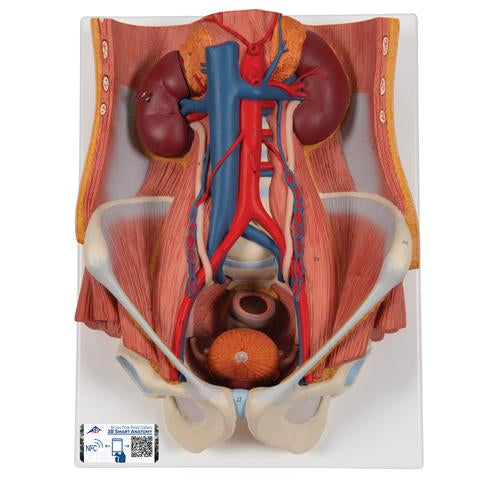

This Urinary System all-in-one-model shows:

- Structures of retroperitoneal cavity

- Large and small pelvis with bones and muscles

- Inferior vena cava

- Aorta with its branches including iliacal vessels

- Upper urinary tract

- Rectum

- Kidney with adrenal gland.

One front half of a kidney is removable from the anatomical model of the urinary system. With easy to change male insert (bladder and prostate, front and rear half) and female insert (bladder, womb and ovaries, 2 lateral halves) the Urinary System model is a great teaching tool. Parts are numbered on the Dual Sex Urinary System.

Dual Sex Urinary System model on baseboard.